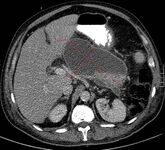

Coleção necrótica infectada, não totalmente encapsulada, no dia 20 após o início da doença

Gut. 2017 Nov;66(11):2024-32; usado com permissão